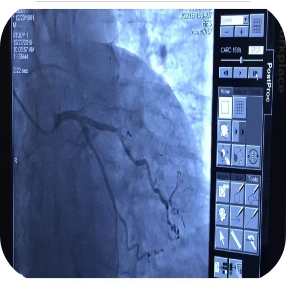

冠心病:冠心病(包括急性胸痛)的诊断和治疗是该科的传统强项,建立了胸痛中心。2015年全市首先开展冠心病介入诊疗。冠心病专业组致力于新技术、新业务的不断探索。将逐步开展冠脉血管内超声系统(IVUS)、冠脉旋磨术、慢性完全闭塞病变(CTO)的逆向介入治疗等。

1.冠状动脉造影术

2.冠状动脉腔内血管成形术、冠状动脉支架置入术、药物球囊置入术